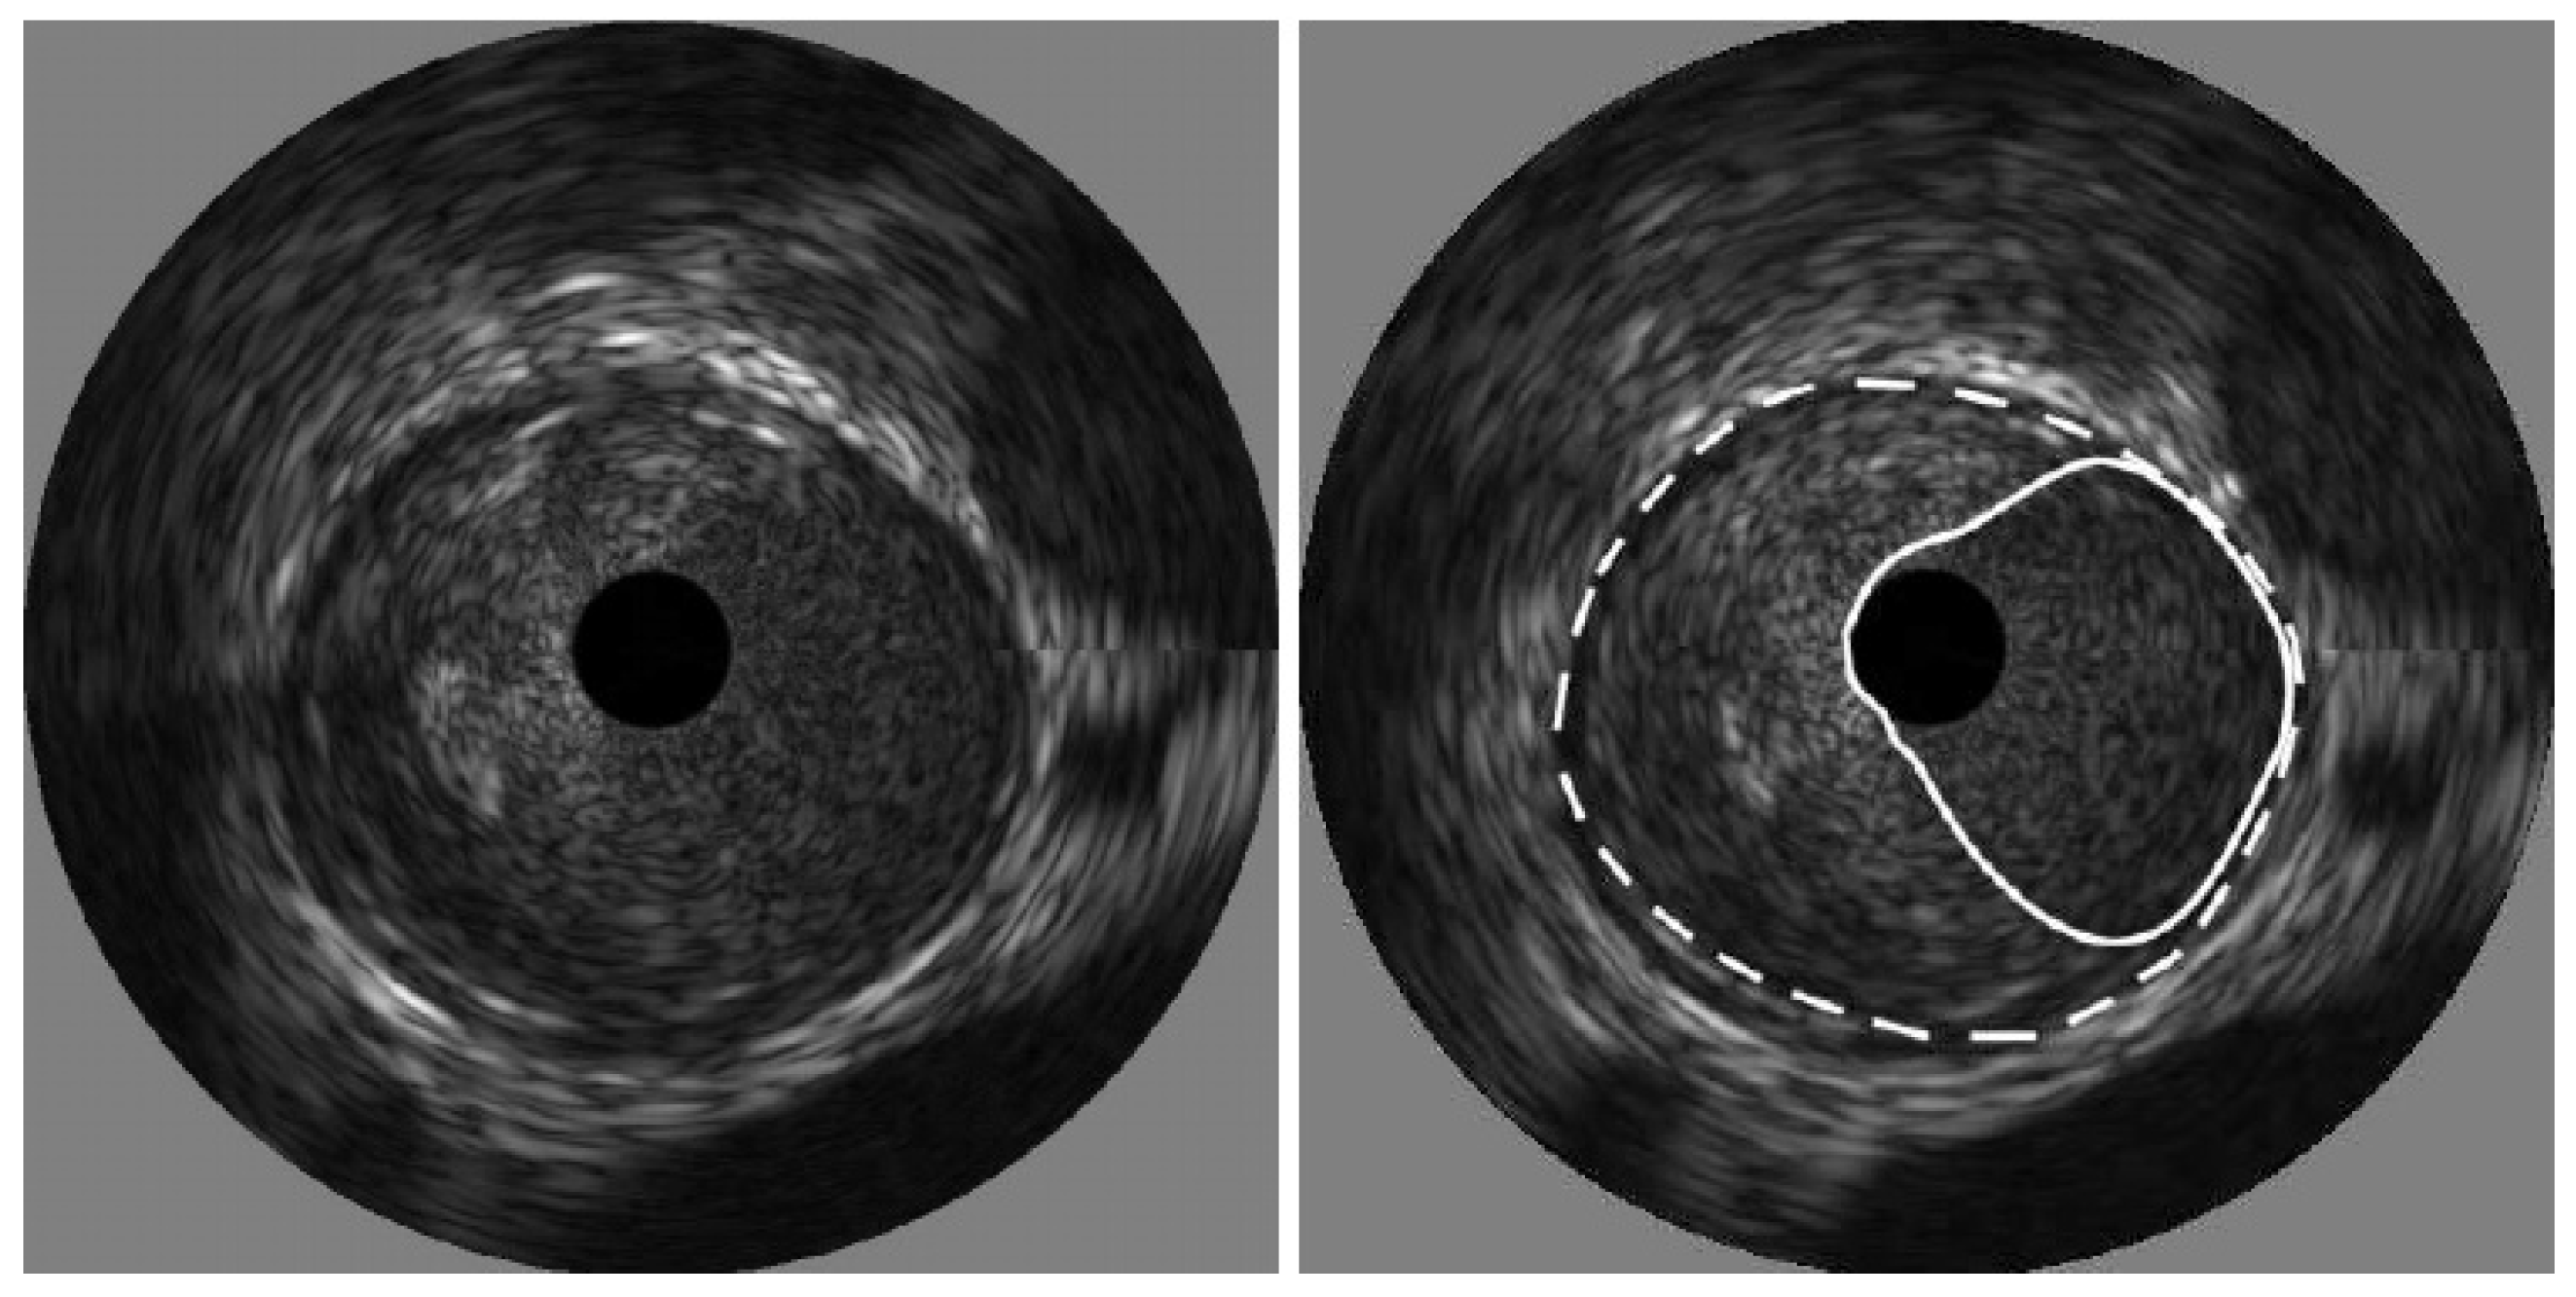

1. Introduction